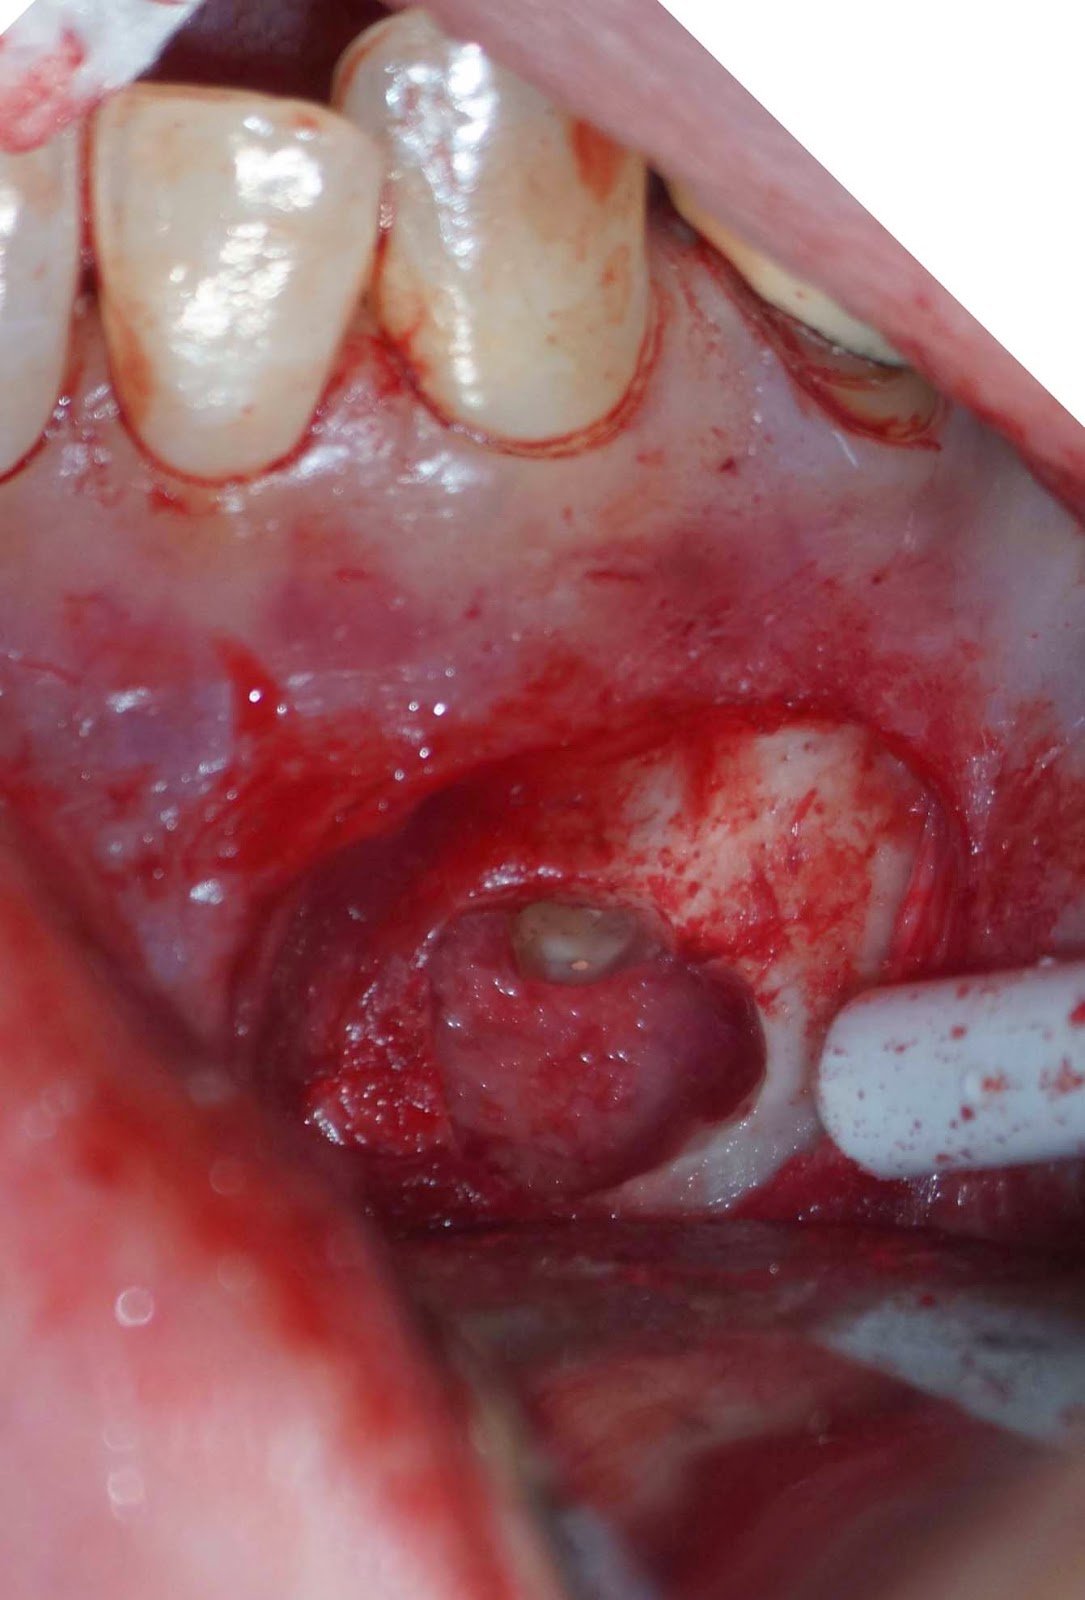

DX: Prior RCT with possible periapical cemental dysplasia. Apical surgery recommended with biopsy.

Biopsy report indicated Periapical Cemental Dysplasia (anterior focal osseous dysplasia) Recurrence would be unusual, but other areas of dysplasia can arise as well as truamatic bone cysts are also common.